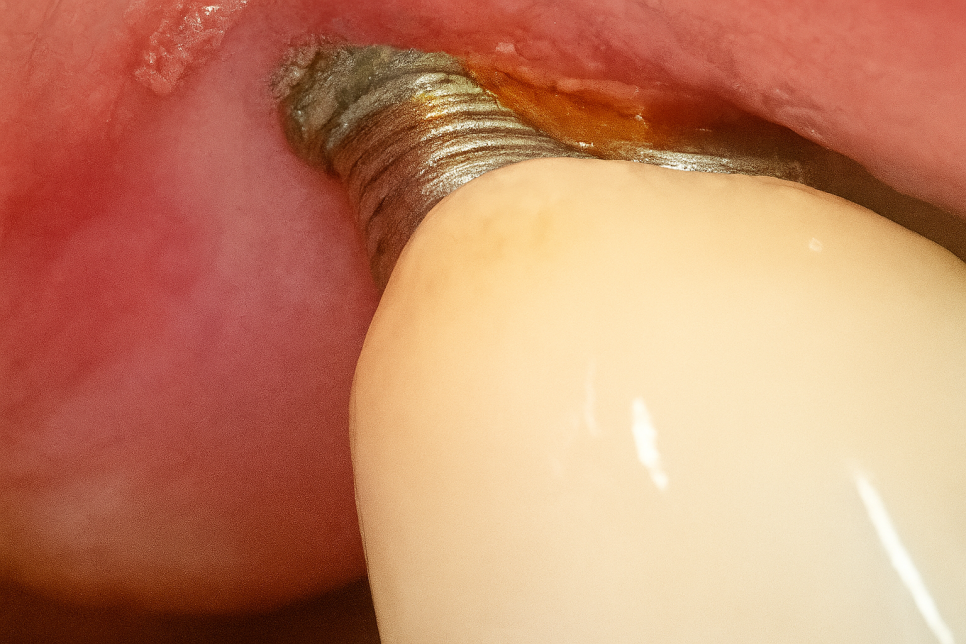

발산동 치과 예시 사진처럼 임플란트를 심은 후, 주변에 염증이 생겨나 뼈가 파괴되면 나사산이 겉으로 드러나게 됩니다.

그 정도가 심해지면 임플란트 자체를 사용하기 어렵기에 개선이 필요하죠.

나사의 윗부분이 치조골 밖으로 드러나 있기 때문에 이를 보완해 줄 방안이 필요하죠.

이런 경우, 소량의 골이식과 함께 PDRN를 사용할 수 있습니다.